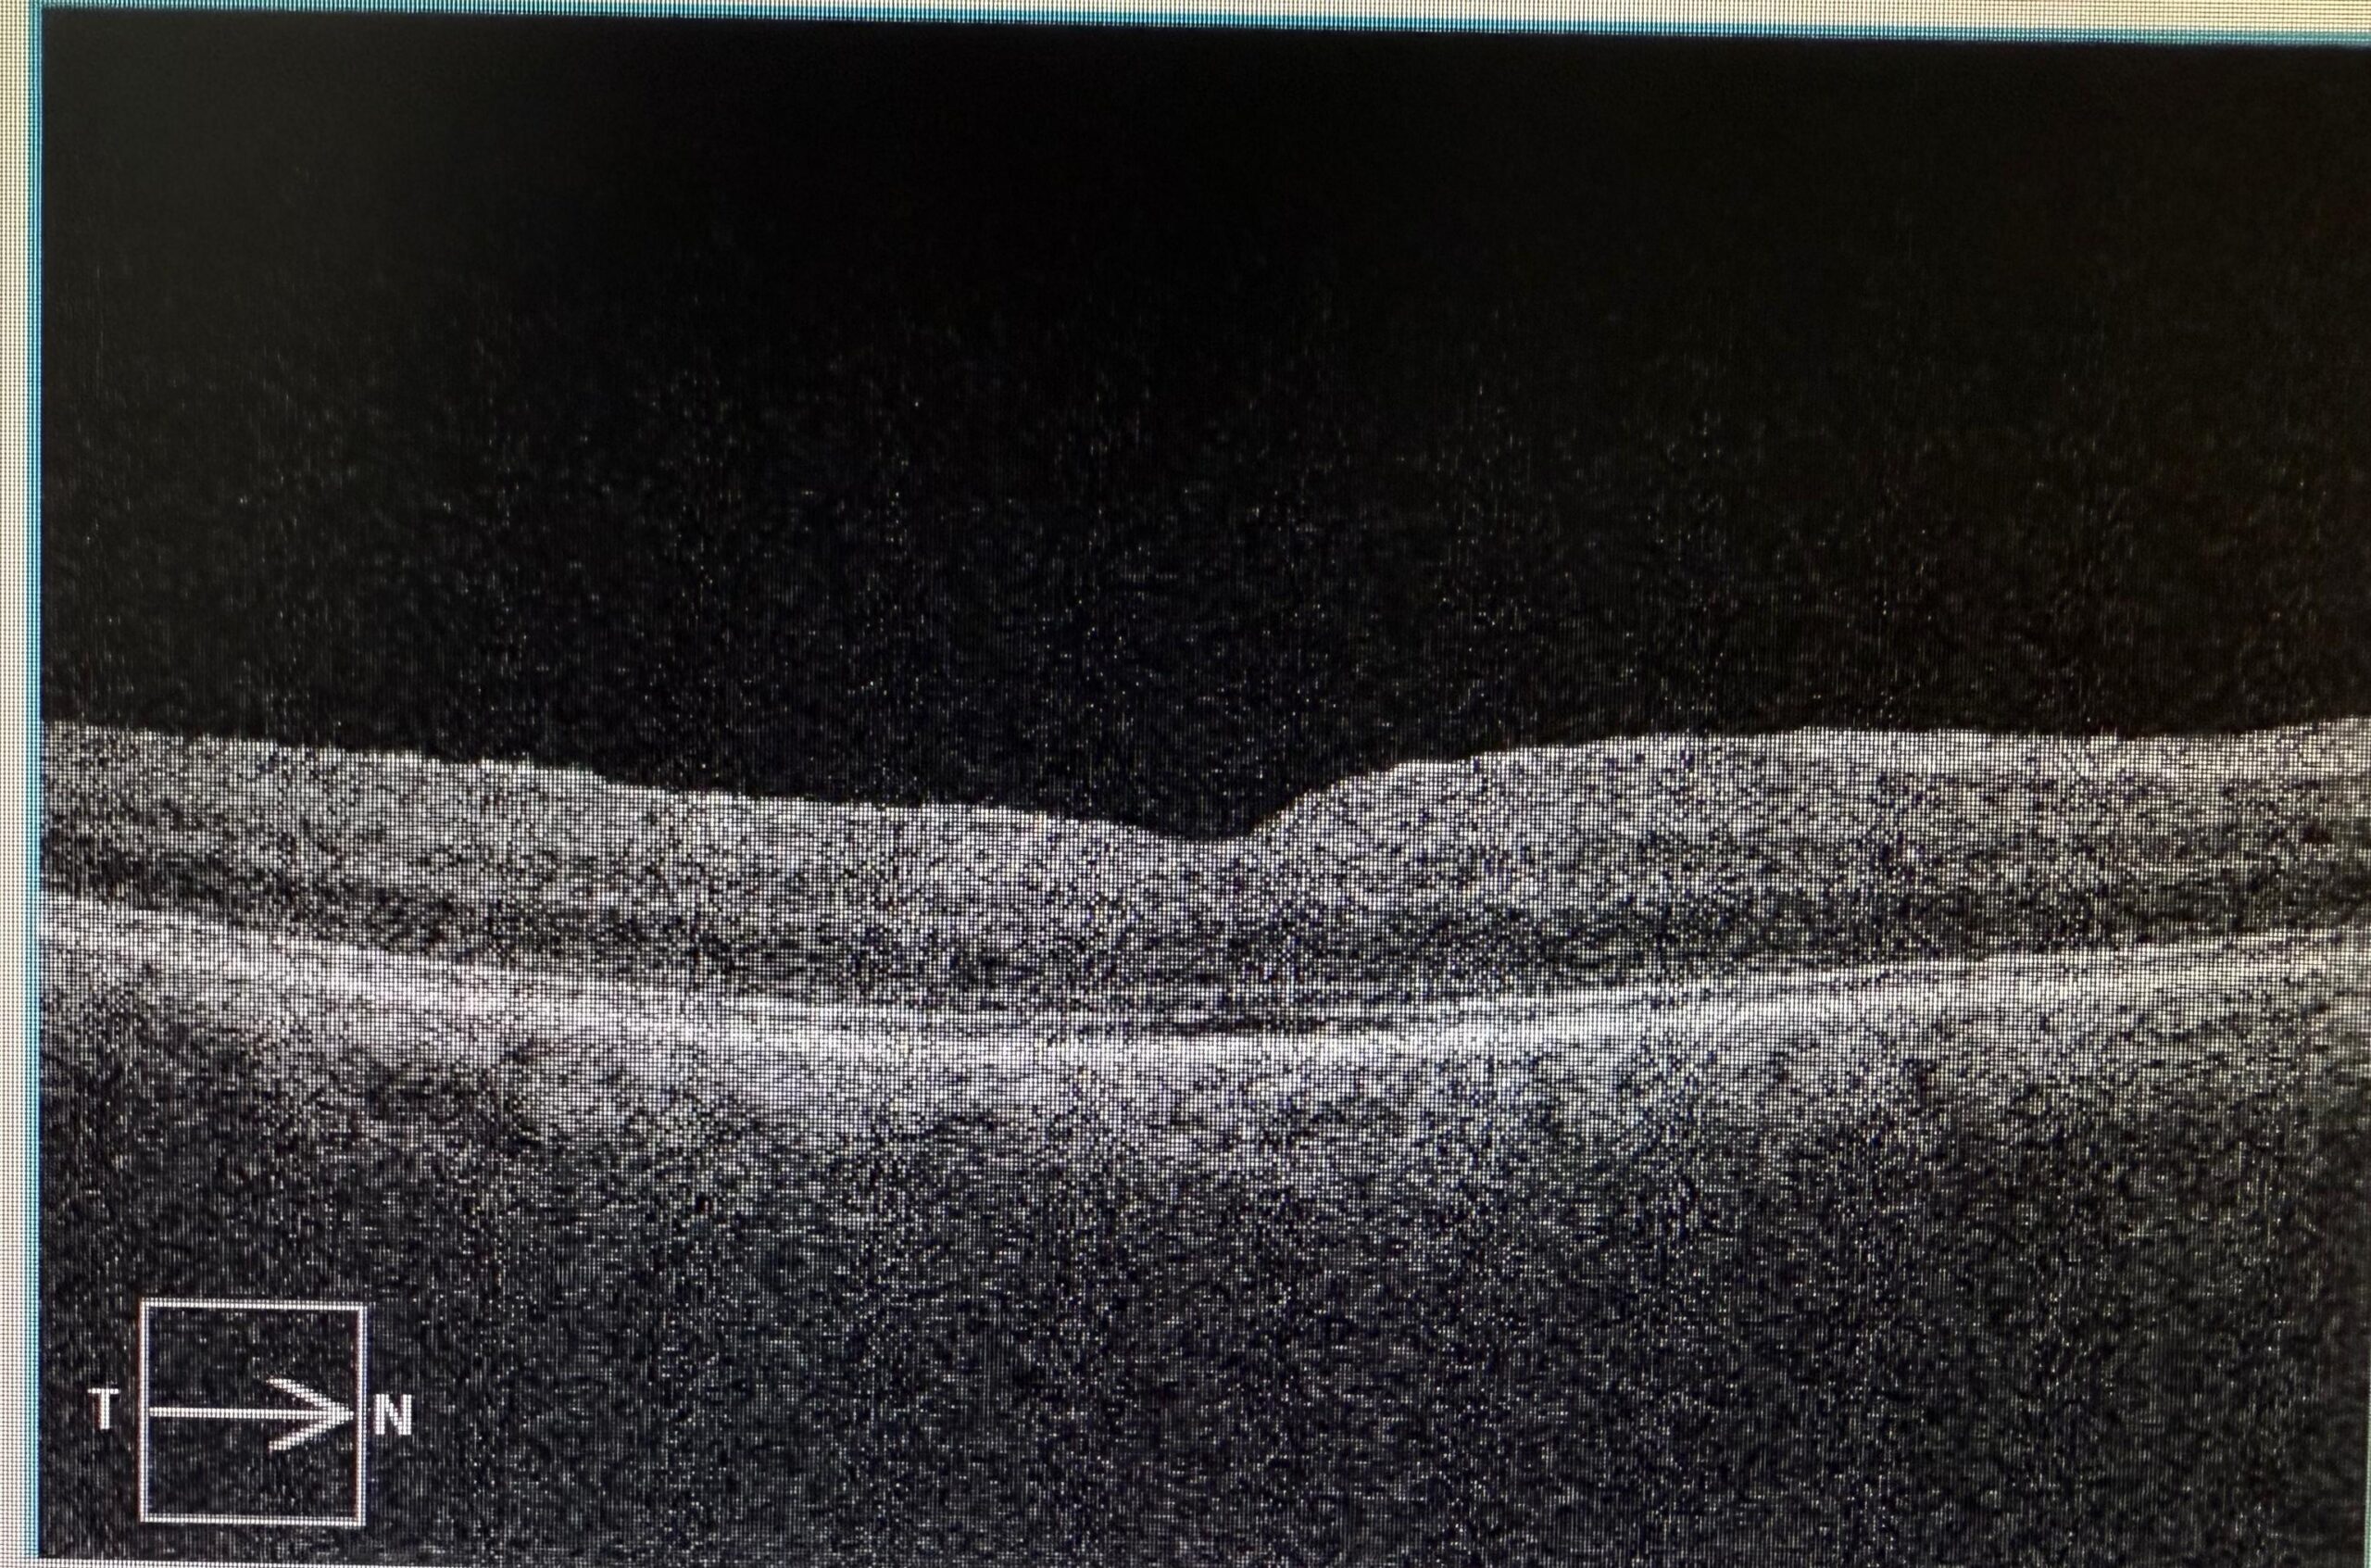

Accurate diagnosis is the foundation of successful retinal care. Our centre is equipped with the latest imaging modalities to detect and monitor retinal diseases with unparalleled precision.

Together, these imaging systems allow us to detect diseases early, plan accurate treatment, and track response to therapy effectively.

OCT scan, Retinal Photography, FFA, and B-Scan.